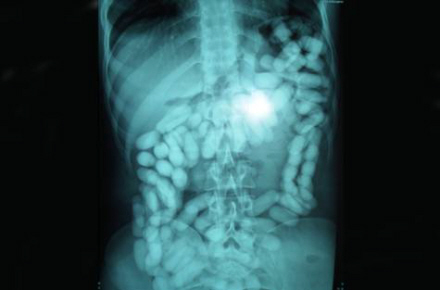

De sluger fra 500 gram og op til et kilo narko, mens én mand er taget med hele 1,233 kilo narko i organerne. Typisk smugles kokain, men også heroin finder vej til danske misbrugere i smuglernes maver.

Det er tydeligt at se poserne med narko på scanningsbilleder